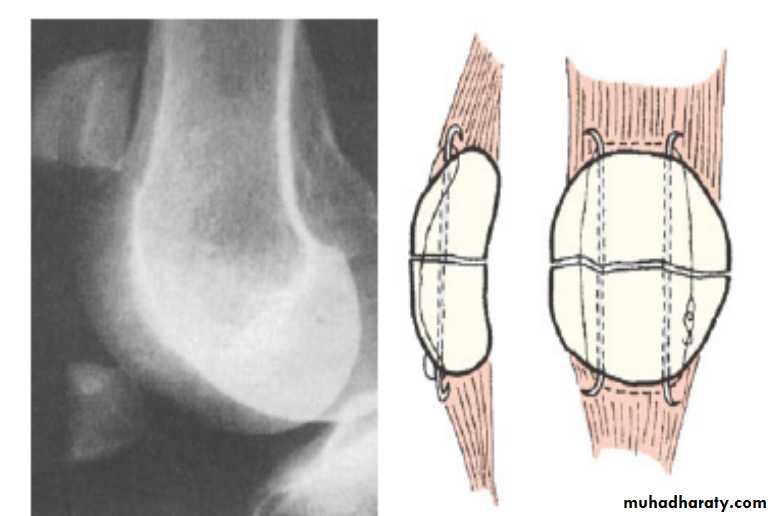

Fractures of patellait can be caused either by:

A- direct force :lead to undisplaced crack or comminuted fracture and here the extensor expansion usually remain intact (the patient can elevate straight leg).B- indirect force :

lead to transverse fracture with gap between the fragments Caused by resisted extension( sudden contraction of the quadriceps muscle against resistant ).

Associated with tears of collateral extensor expansions and failure of extensor mechanism (patient cannot elevate leg straight).

Treatment :

For the fractures caused by direct force :

In undisplaced or minimally displaced fracturesThe treatment is by p.o.p cylinder holding the knee straight should be applied for 3–4 weeks.

during this time quadriceps exercises are to be practised, haemoarthrosis should be aspirated. Severely comminuted and

displaced fracture

treated by

internal fixation or delayed patellectomy.

Internal fixation

Indirect force:

Operation is essential.

Through a longitudinal incision the fracture is exposed and the patella repaired by the tension-band principle .The tears in the extensor expansions are then repaired.